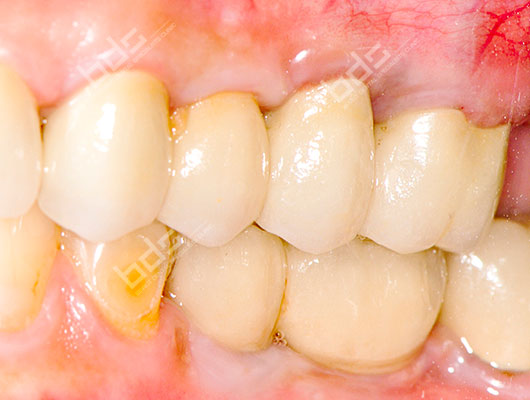

Case 1: After

Case 3: After

Case 2: After